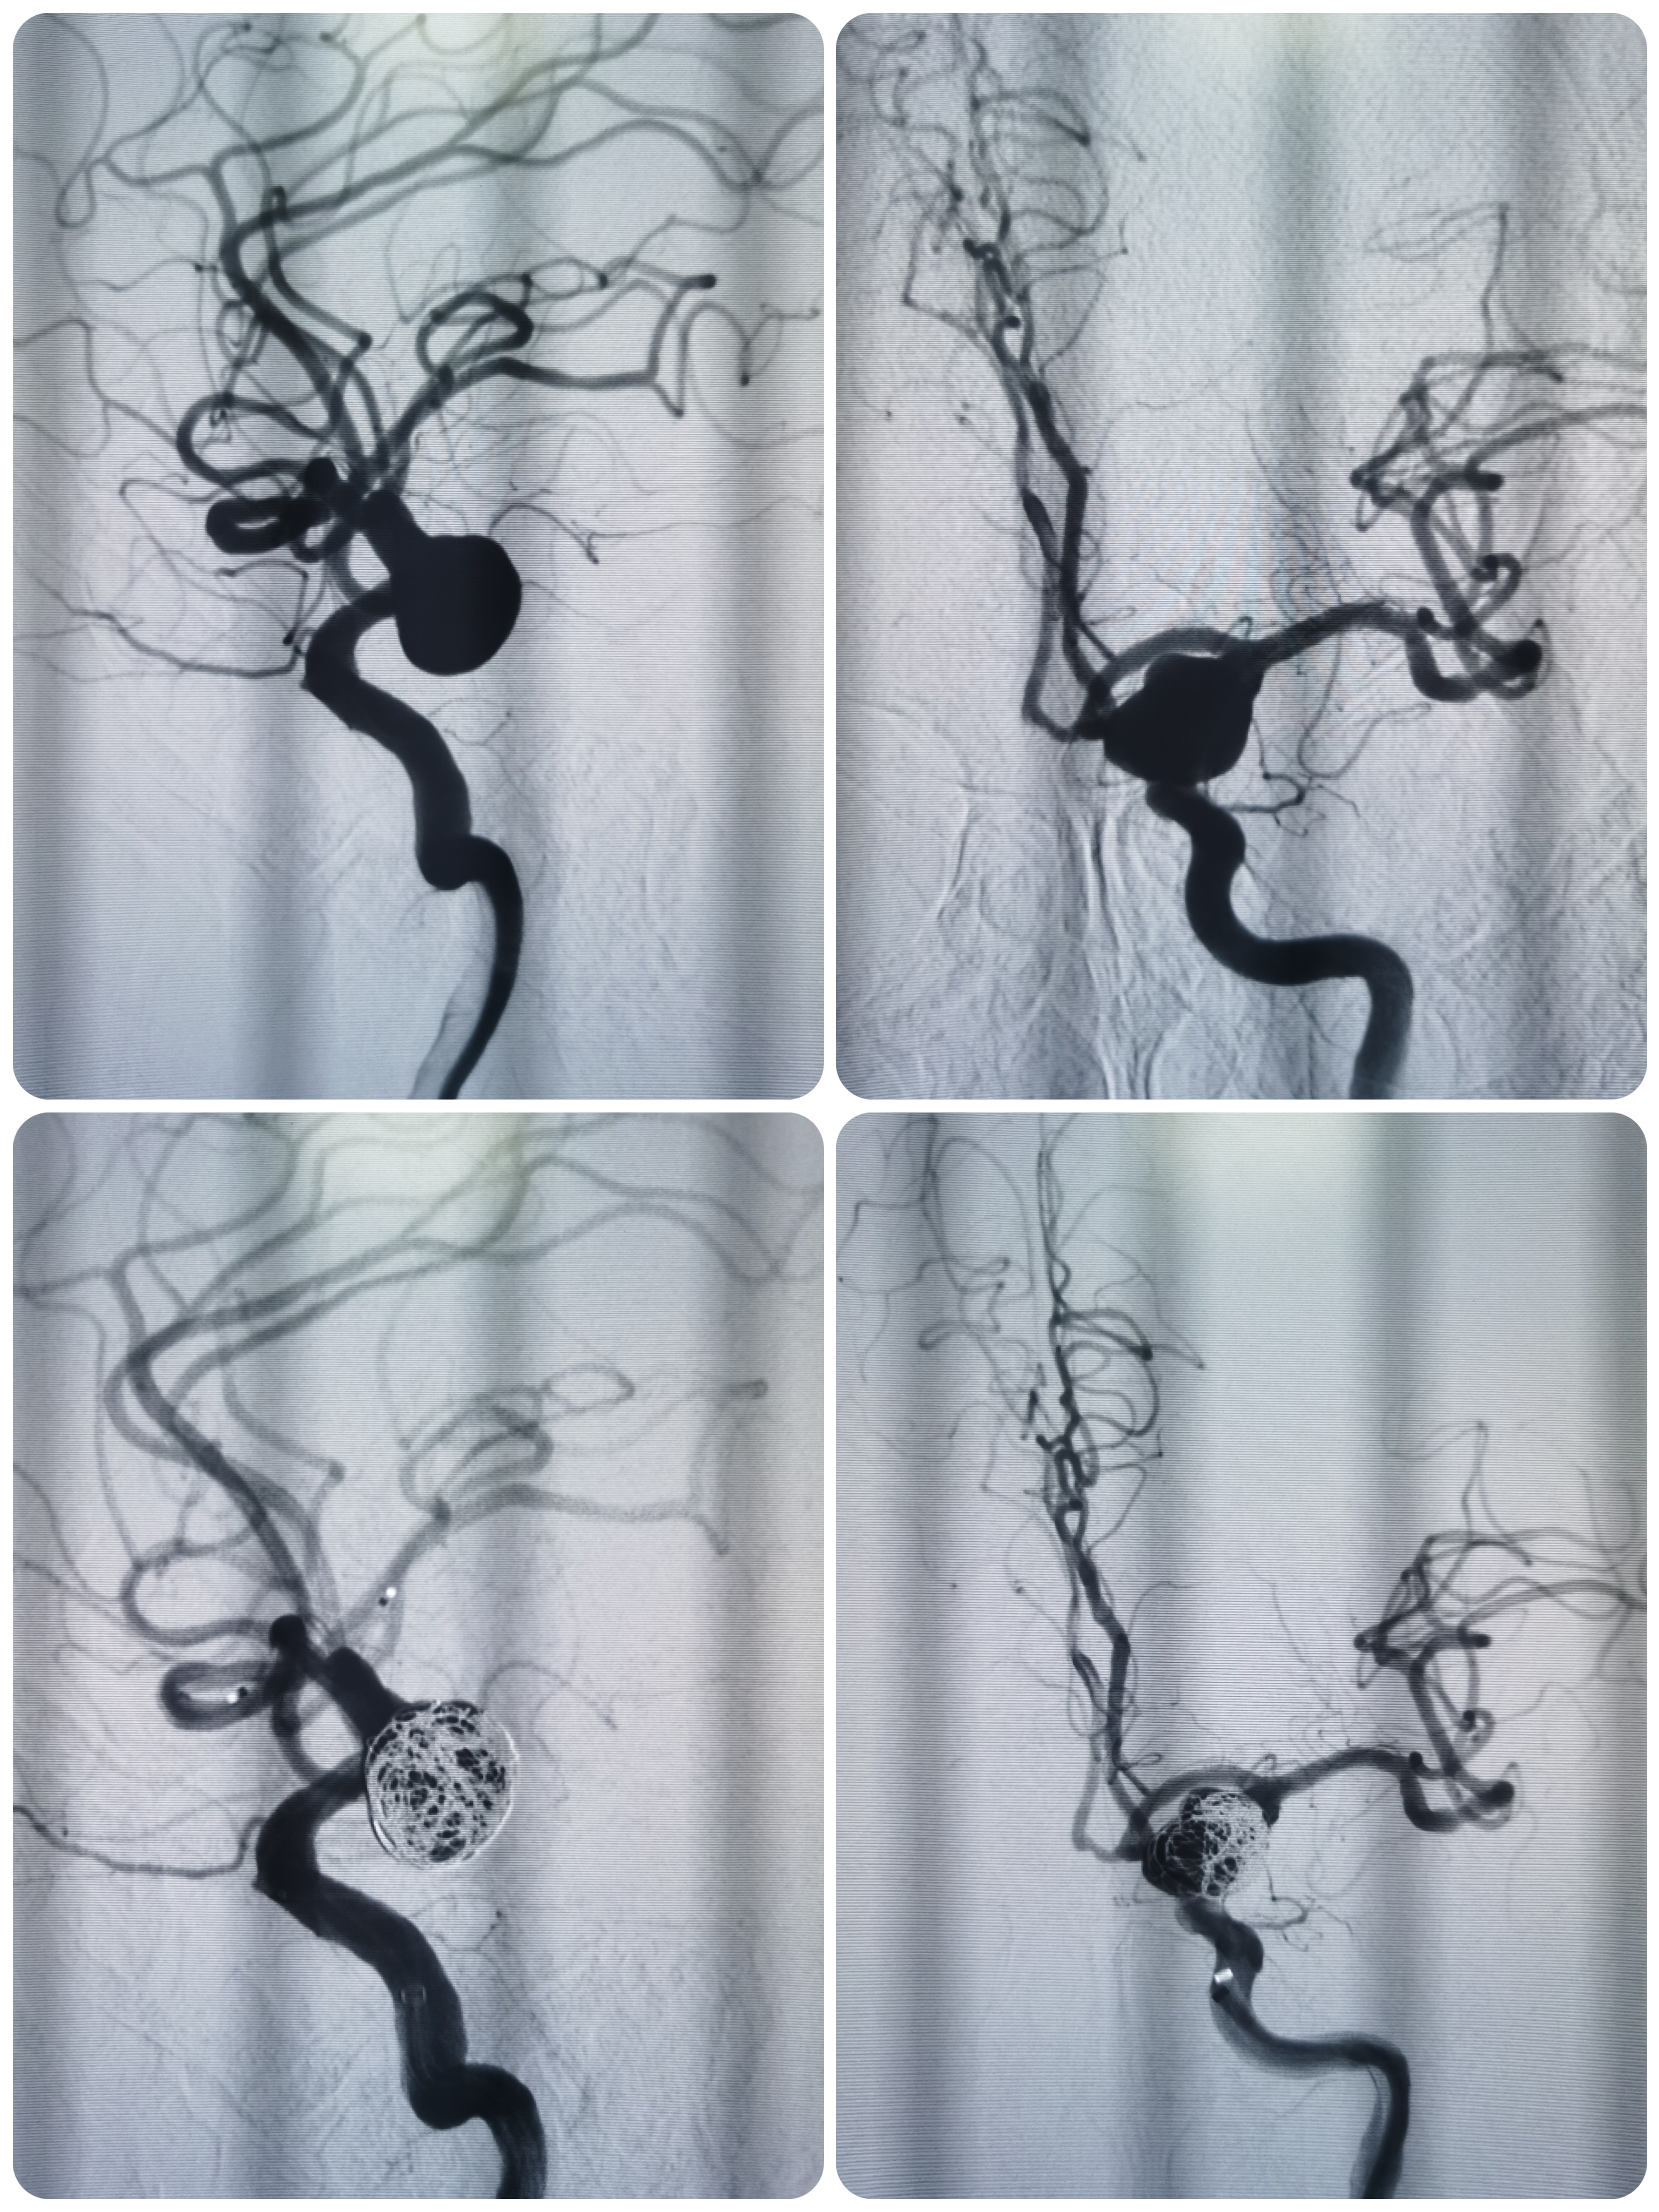

路途下中间导管到位至于左侧颈内动脉海绵窦段,微导丝携SL10微导管于瘤内成攀技术顺利到达左侧大脑中动脉远端。

微导管塑形后送入动脉瘤腔内,首枚填入12*30成蓝圈,再依次填入10*30,9*30,8*30弹簧圈,造影见瘤体上部致密填塞,载瘤动脉通畅。

利用微导丝将栓塞微导管再重新选入动脉瘤体下部,依次填入7*30,7*20弹簧圈,复查造影见动脉瘤大部填塞,瘤内造影剂滞留明显载瘤动脉通畅。

术后即刻造影见动脉瘤栓塞较完全。

术后造影见动脉瘤栓塞较为完全,载瘤动脉通畅,遂未再植入支架,逐渐撤出各级导管,缝合股动脉结束手术。